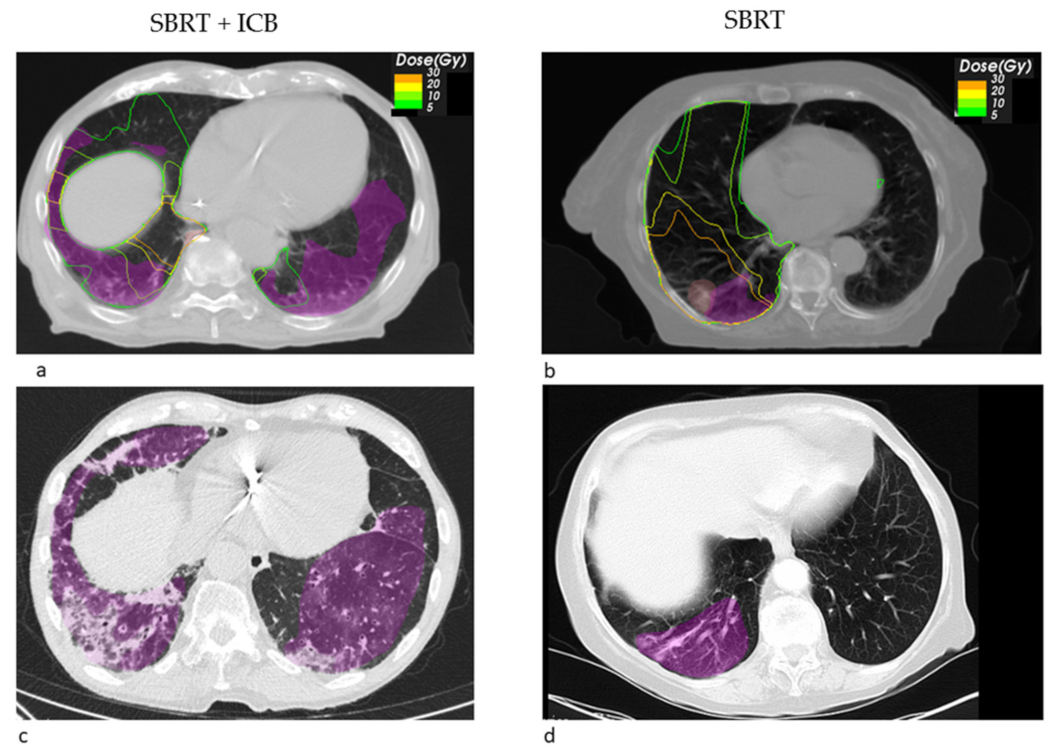

Looking at the dosimetric results in more detail, we observed a trend towards a decreased fraction of the pneumonitis volume receiving a high dose of EQD2 > 20 Gy SBRT + ICB (22.26% vs. 71.14%, p = 0.549), whereas the mean low dose fraction with EQD2 < 10 Gy was numerically larger (39.02% vs. 26.99%). Figure 1 shows the pneumonitis extensions and EQD isodoses for two exemplary cases from both groups. For the depicted SBRT + ICB case, the pneumonitis affects both lungs with a rather small single-sided GTV distant from the resulting radiological changes. For another patient, who received SBRT with 45 Gy in 3 fractions to a small left-sided tumor, we also found bilateral extent of pneumonitis, as shown in Figure 2. This patient received additional SBRT for liver metastasis at the same time with the same dose fractionation regime; however, the extent of pneumonitis does not correlate with the dose distribution. For dosimetric analysis, we used sum doses to prevent overestimation of the effect attributed to the lung SBRT. A third patient also showed the bilateral extent of pneumonitis. This patient received hypofractionated, contralateral mediastinal RT with 45 Gy in 15 fractions a month prior to SBRT. Since the extent of the pneumonitis volume in the contralateral right lung is more likely caused by the irradiation of the right side, we considered only the pneumonitis contour from the left SBRT side for analysis. However, to not overestimate the dosimetric effect of SBRT alone, we used the sum EQD2, as shown in Figure 3a, for dosimetric evaluation as well.

Figure 1. Transversal radiotherapy (RT) planning CT slices showing the EQD2 isodoses and pneumonitis contours (magenta) and GTV contours (light red) for a SBRT + ICB case (a) and for a SBRT case (b). Exemplary transversal slices from the follow up CT showing the pneumonitis and its contours (magenta) for the SBRT + ICB case (c) and the SBRT case (d).